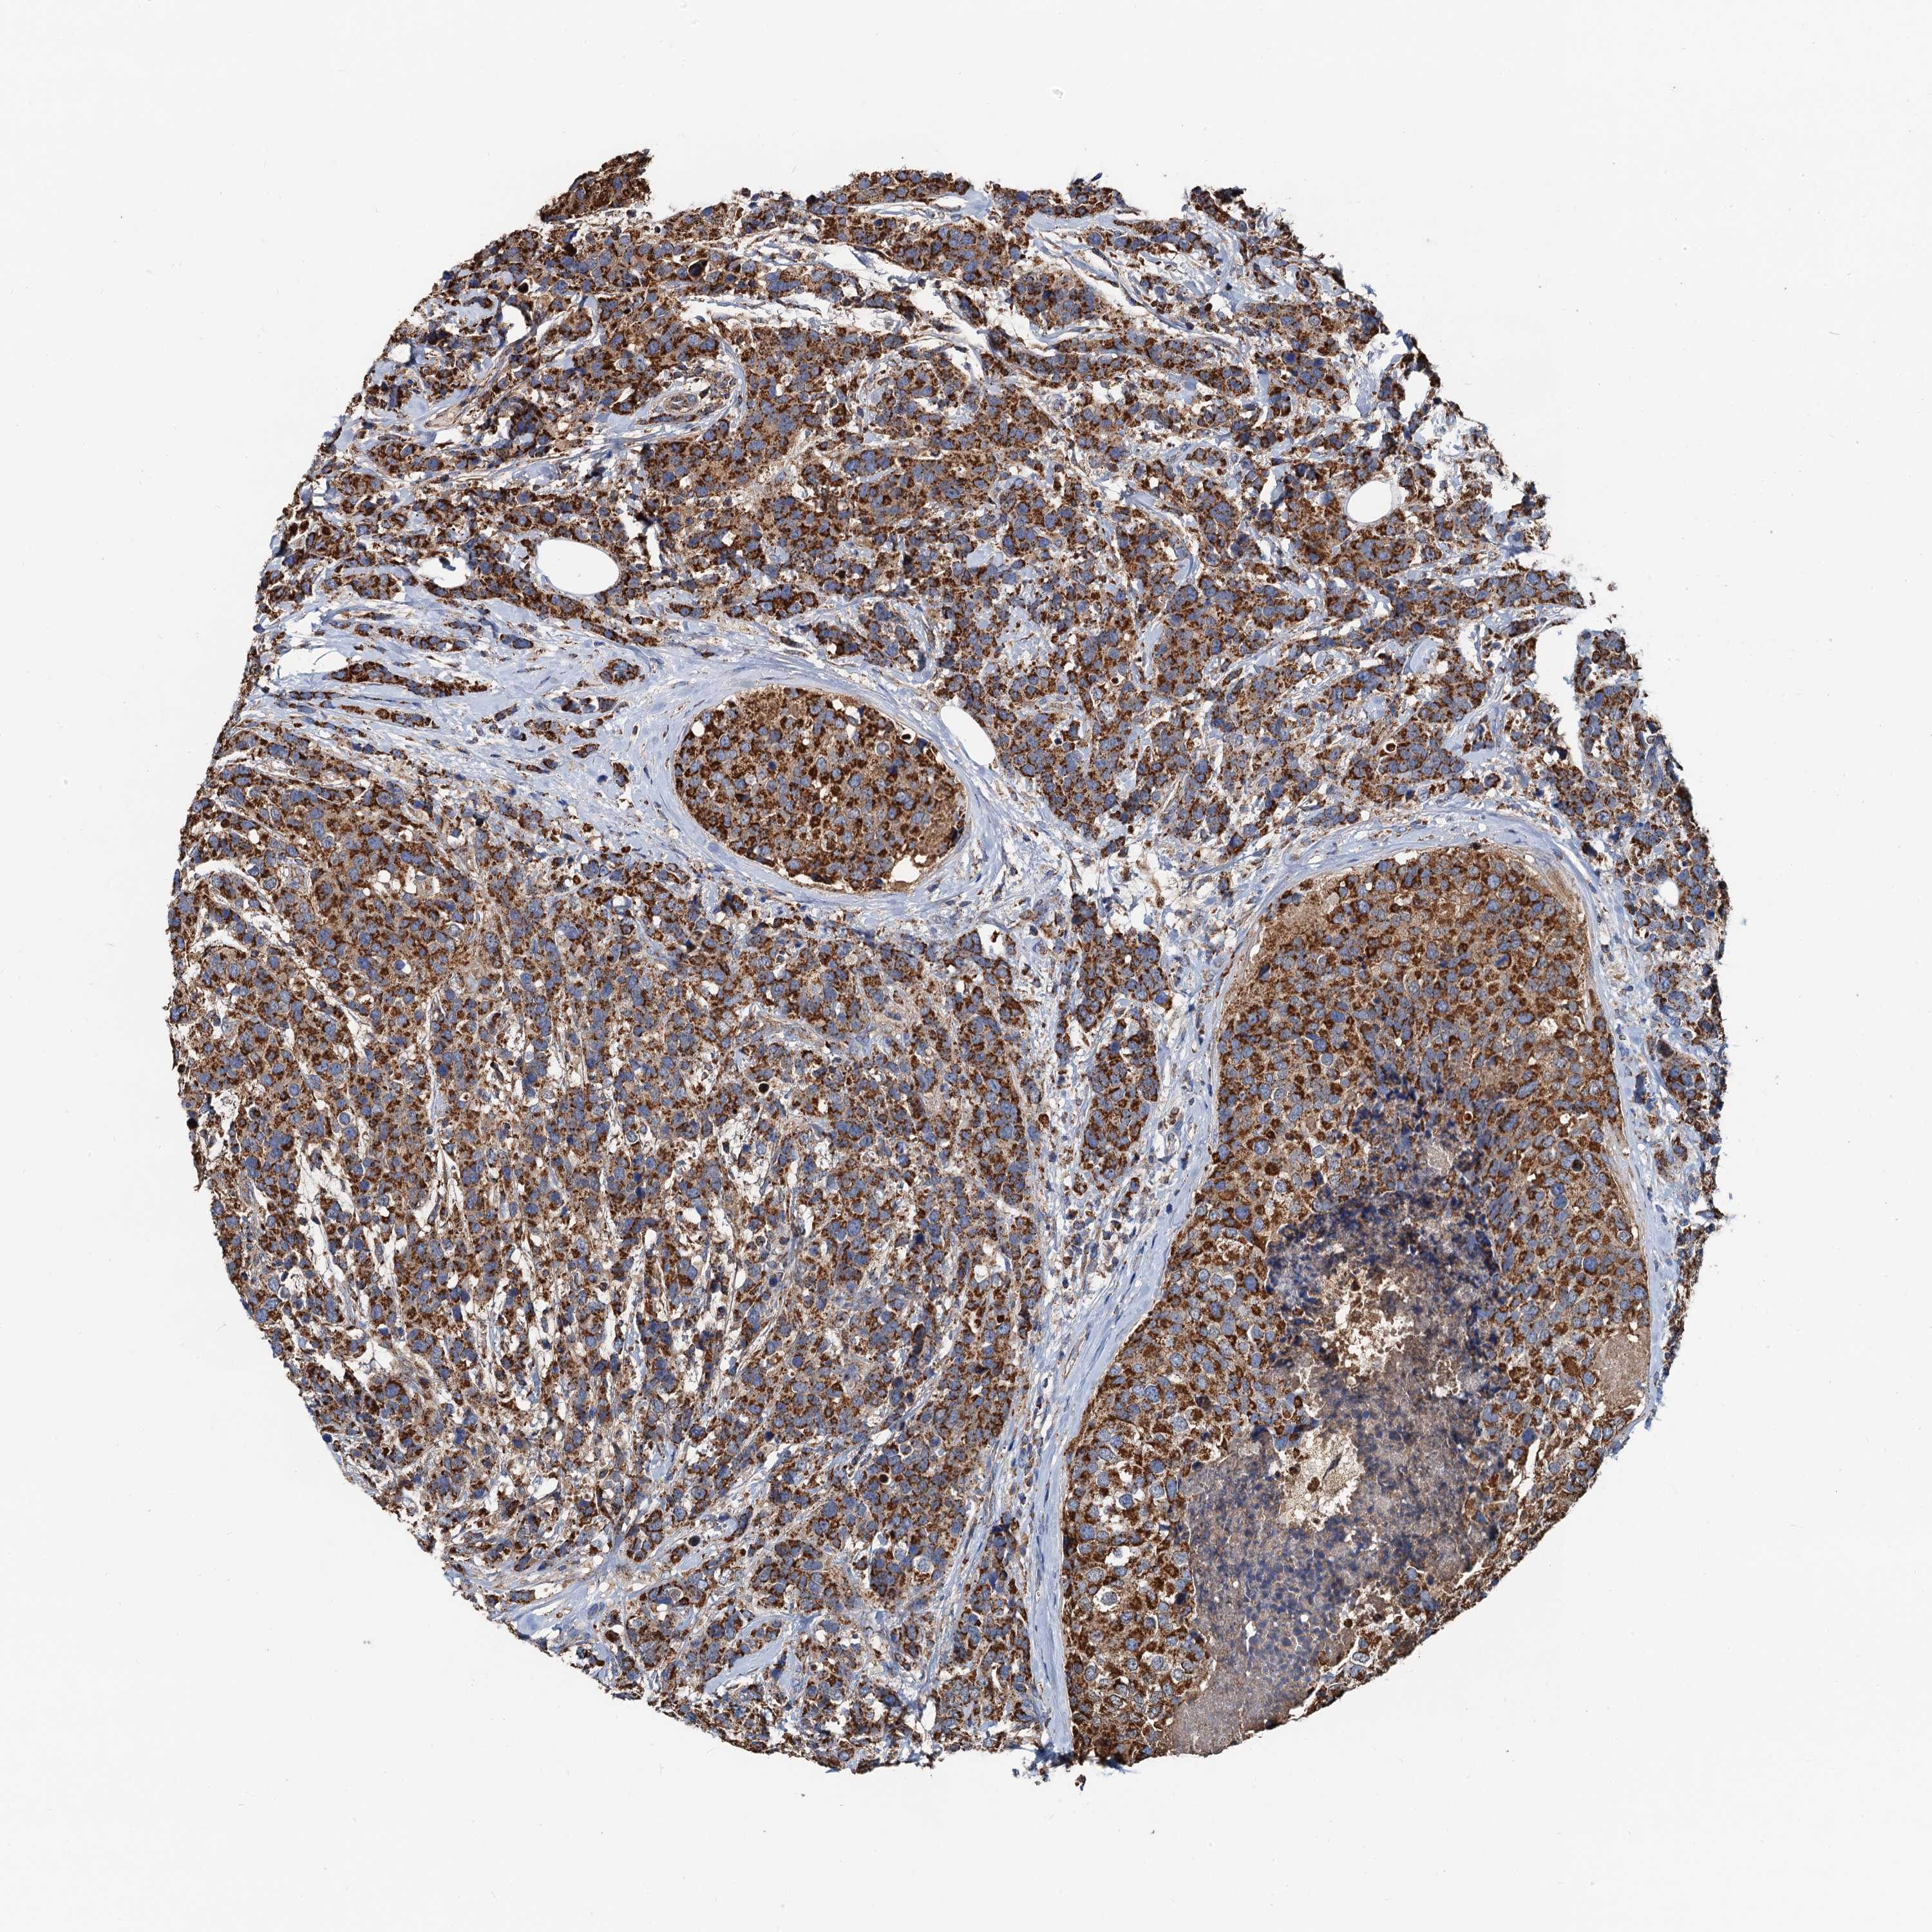

CANCER BREAST CANCER Show tissue menu

BRCA TCGA BRCA VALIDATION PROTEIN EXPRESSION